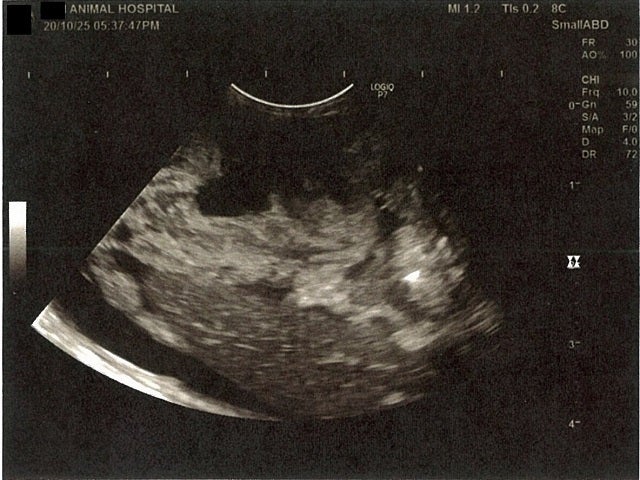

右腎臓周りに腹水が確認できるエコー写真

膵臓周りに腹水が確認できるエコー写真